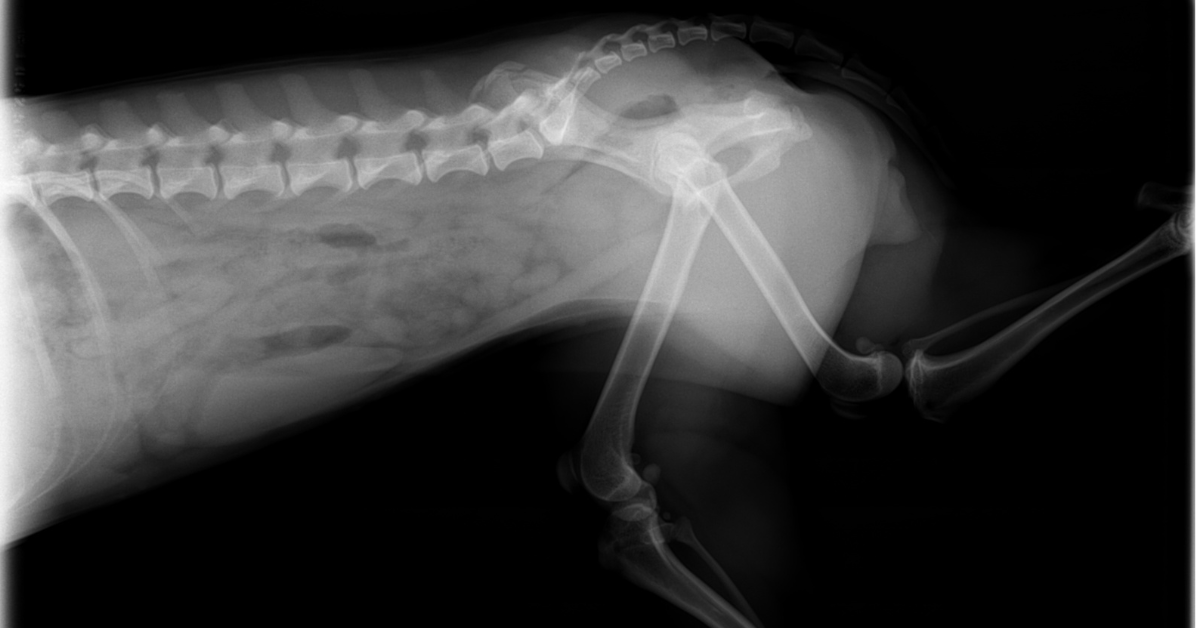

To explain it in simpler terms, the vet will manually exert pressure on the hind legs or by using a device to examine your dog’s mobility and level of discomfort. He will conduct further examinations to look for any grinding noise from the joints. To confirm the diagnosis of hip dysplasia, the vet may ask for an x-ray to be done.

Similar to hip dysplasia, a radiograph will also confirm the hip dislocation. Besides confirming the dislocation, the x-ray will also help determine if a part of the hip has been fractured.